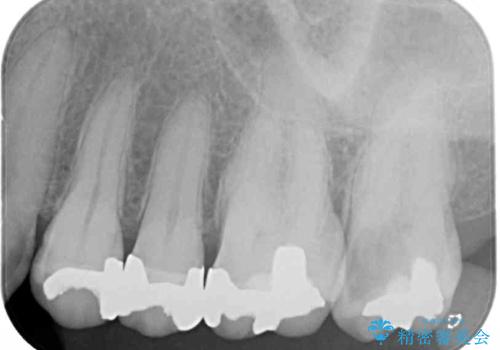

上顎の奥歯は神経にまで虫歯が及んでいる可能性が高かったため、抜髄や断髄の可能性を考慮しながら処置を進め、セラミッククラウンにて補綴することとしました。

上の奥歯は一部神経を取り除くこととなりましたが、残った神経は正常な状態を保つことができました。